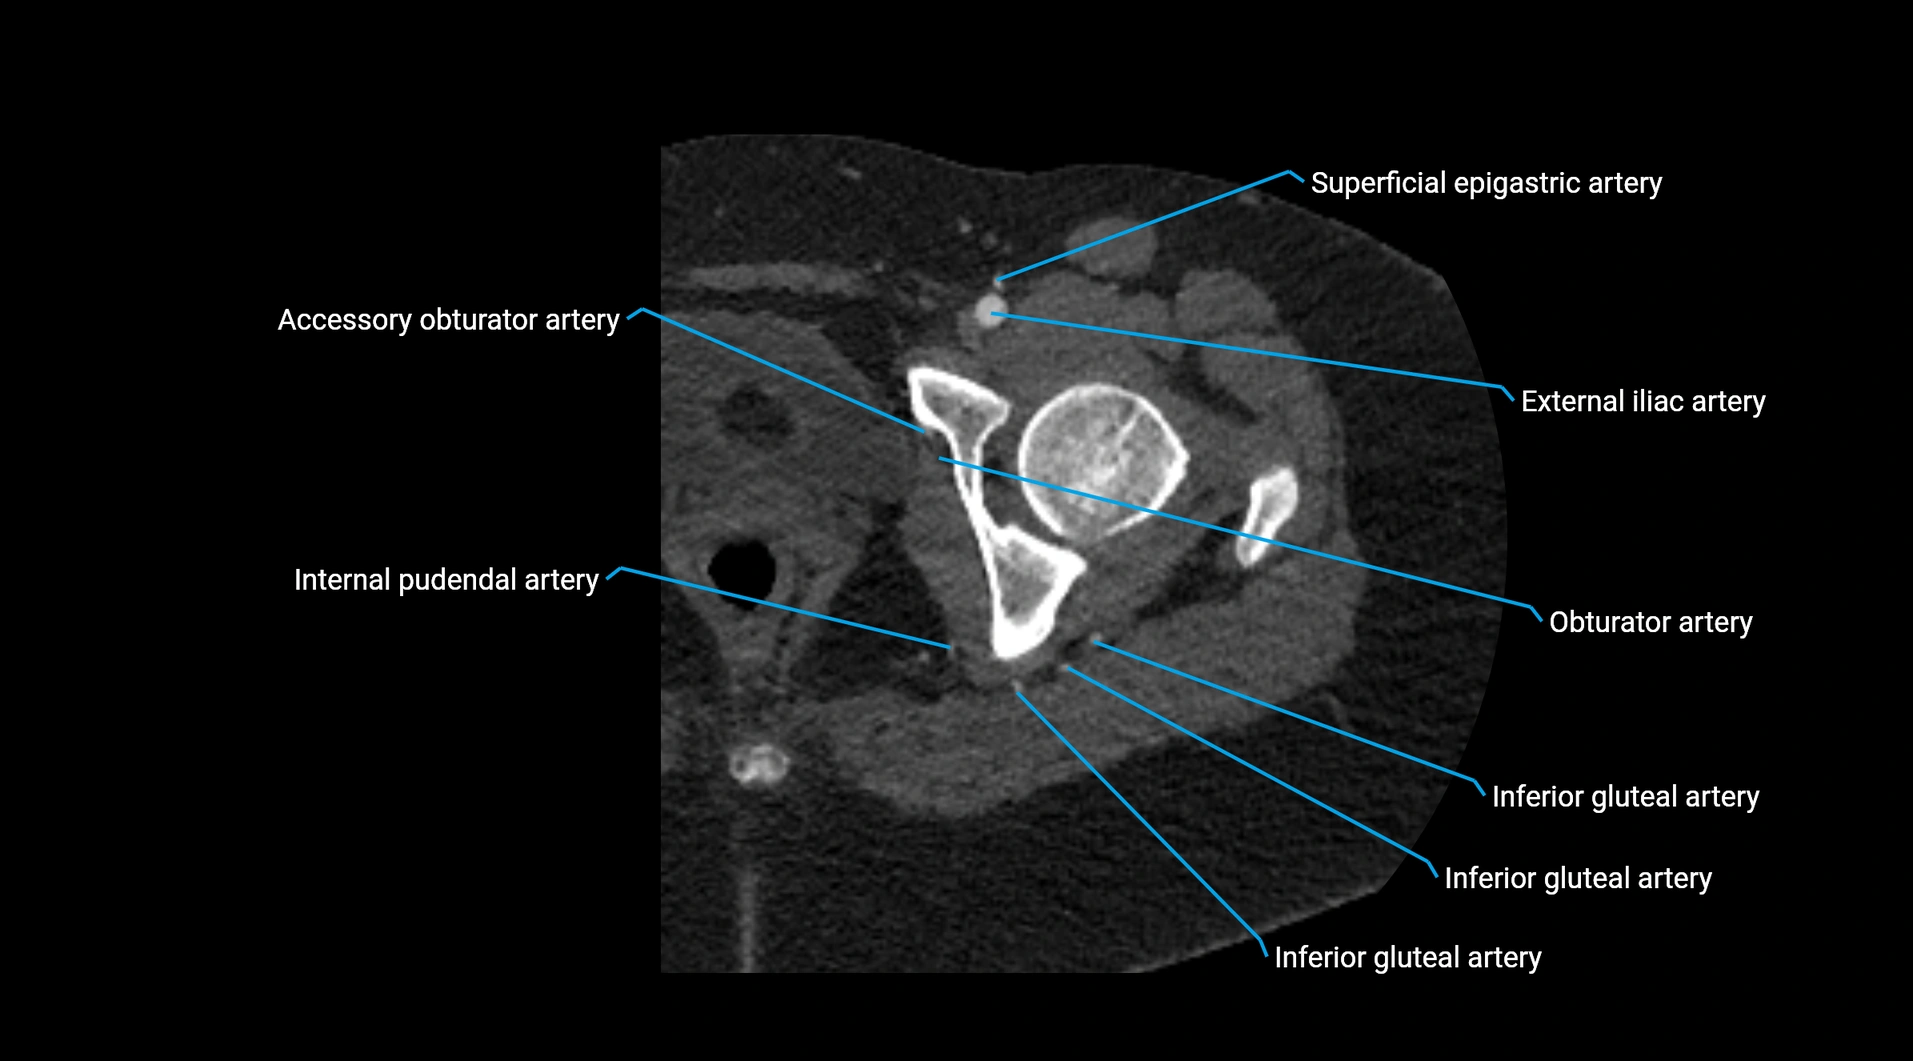

CT images

image